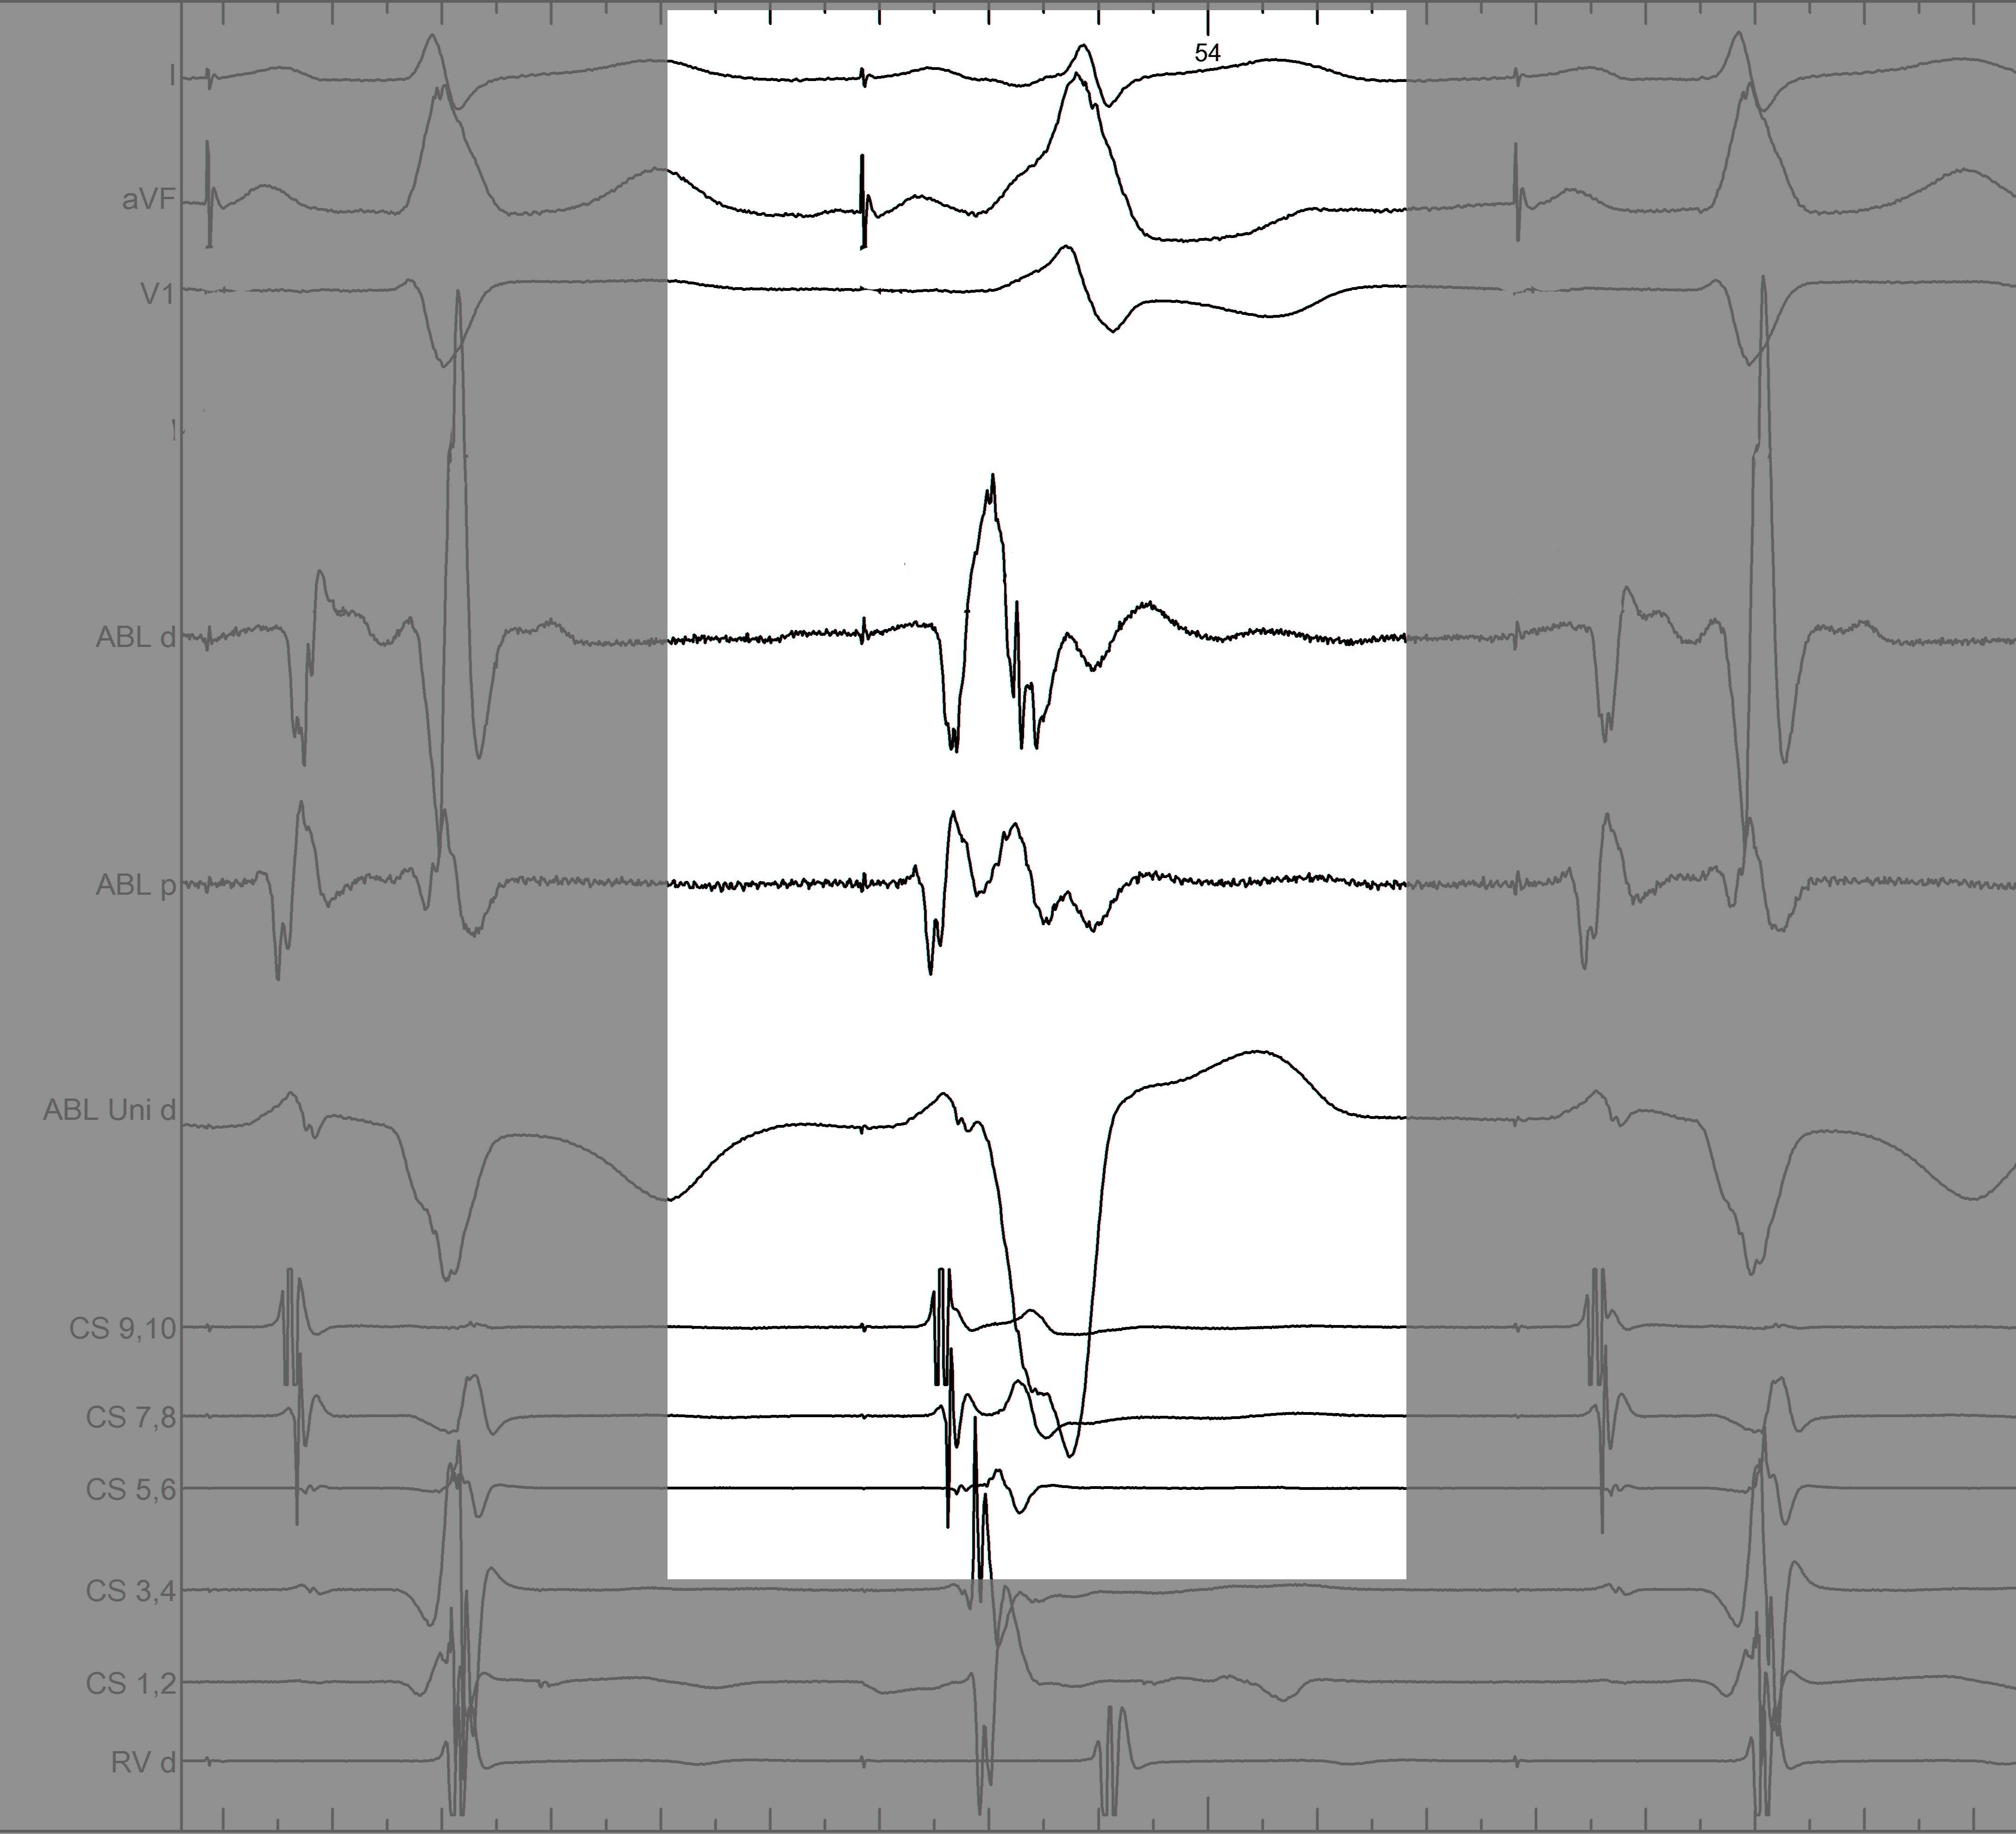

mask1.jpg

Information from other electrodes

mask2.jpg

Unipolar

mask3.jpg

Non preexcited beats

mask4.jpg